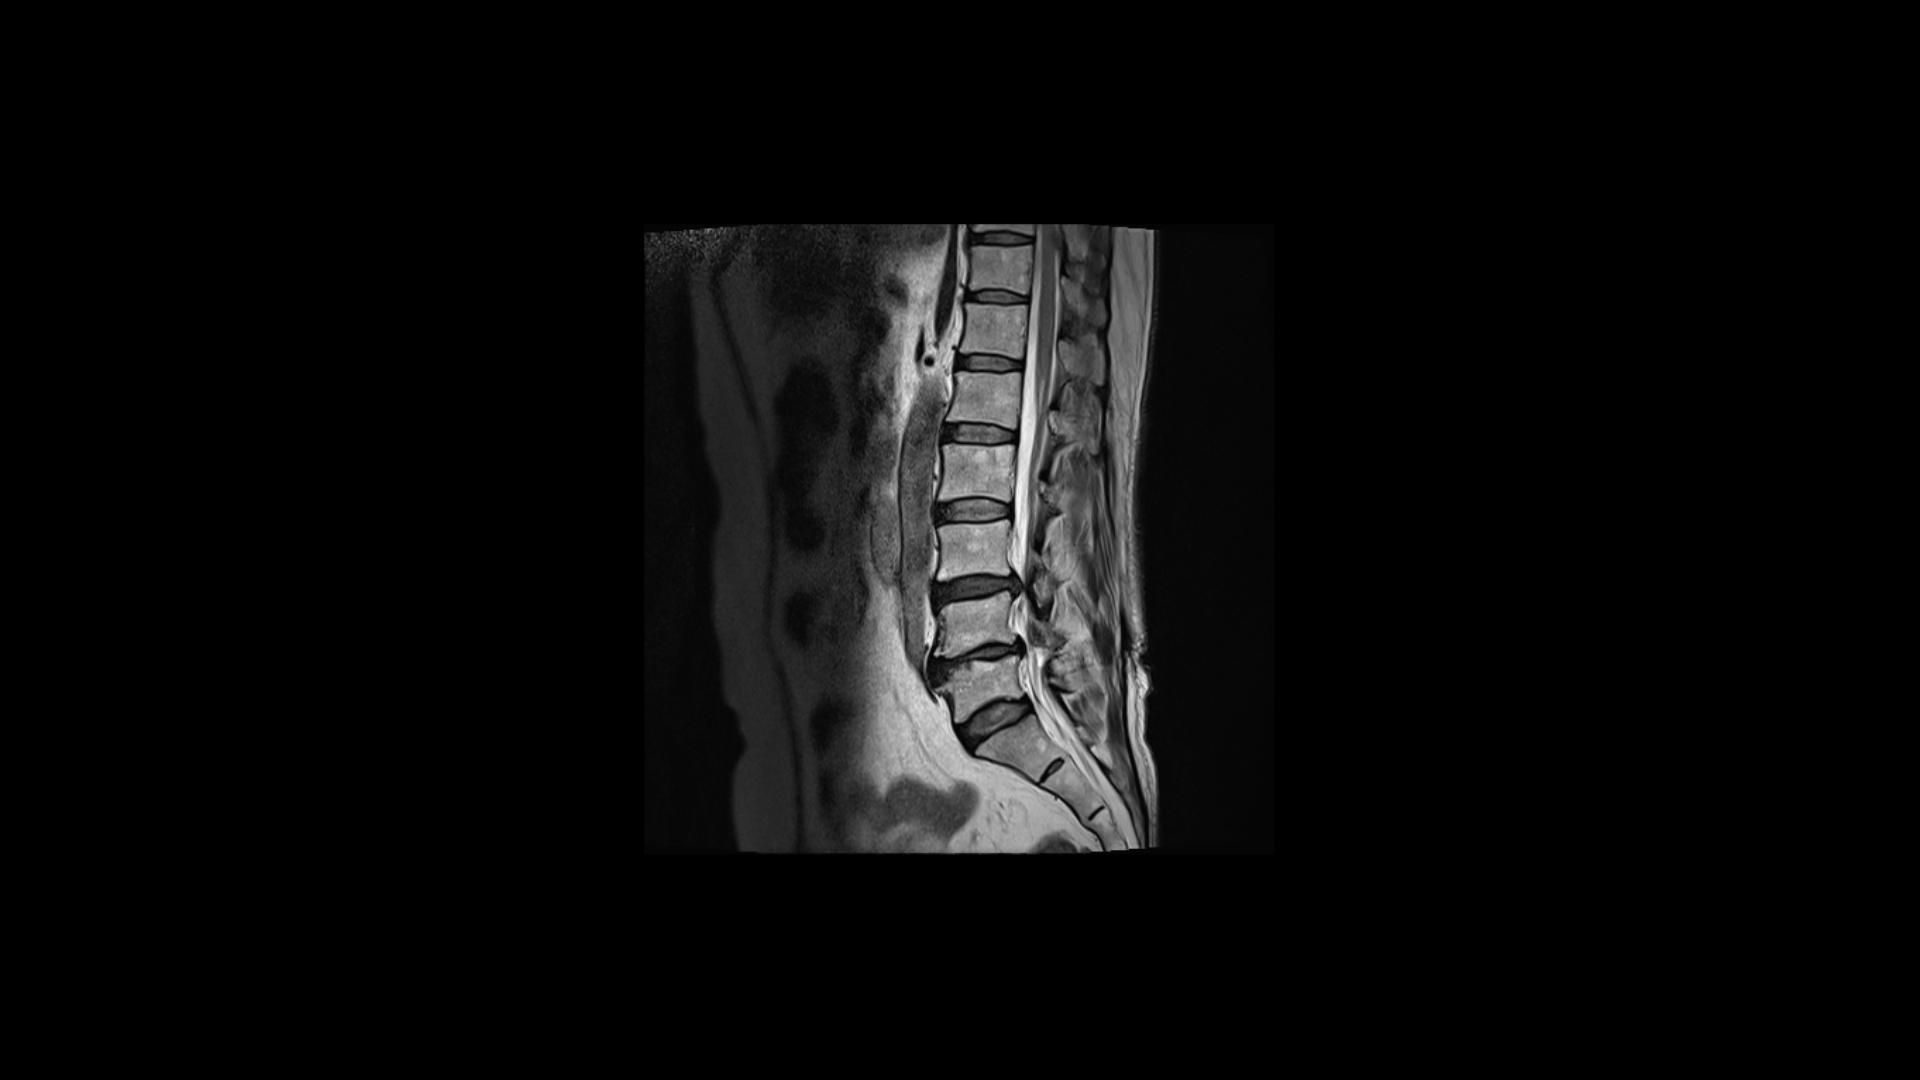

제가 먼저 이 환자분의 상태에 대해 설명드린 후 이분 말씀 더 들어보겠습니다. 이 환자분은 정말 오래된, 본인 표현으로는 30년된 심한 여러 마디의 목디스크와 또 허리에는 2마디의 퇴행성 디스크 및 추간공협착이 있습니다. 목디스크는 MRI로 보면 3번 4번 목디스크가 뼈가 심하게 자라면서 밀려나와있고 왼쪽으로 나가는 신경길을 막고 있습니다.

허리MRI를 보면 두 마디의 퇴행성디스크와 추간공협착이 있습니다.

3번 4번은 왼쪽 중앙으로 밀려나와있고

4번 5번은 왼쪽 신경이 빠져나가는 추간공이 뼈가 자라면서 좁아져 추간공협착이 있습니다.

또 왼쪽 후궁에는 과거에 받은 수술의 흔적도 보입니다.